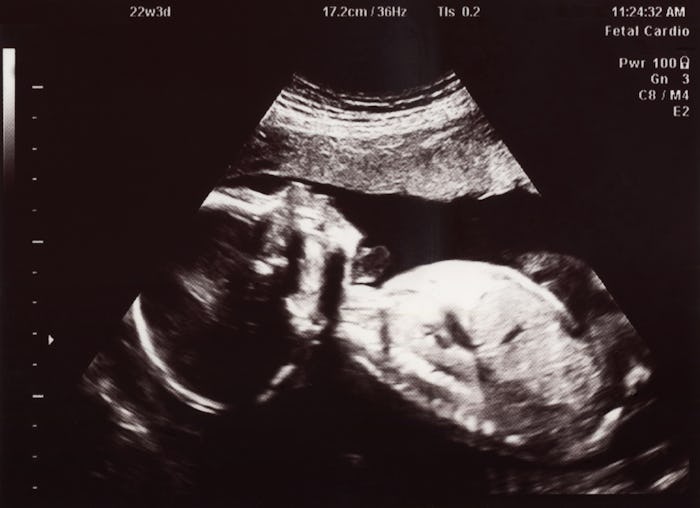

Your baby's life in the womb may be safe and warm, but it's also kind of grody. Seriously, the whole process of growing into a human being includes more than a few icky moments along the way. But this is the grossest thing babies do inside the womb by far, and it's almost never talked about. Are you ready?

Developing babies drink their own pee in the uterus, as noted in The Independent, and I don't think I need to tell you how gross that is. You're welcome to insert your own Bear Grylls joke here, but it's true. A fetus's kidneys kick into action as early as week 11 of development, as explained in The Bump. Although the amniotic fluid is mostly made up of a mother's body fluids in the earliest days of pregnancy, it steadily becomes more and more baby pee. By the end of your pregnancy, the amniotic fluid contains more pee than a water park at the height of summer.

Around week 11 of development, another developmental moment occurs. The membrane blocking your baby's mouth breaks down, as noted by UNSW Embryology. Basically, your baby can start swallowing around the same time your baby starts peeing. Isn't nature magical? But relax, it's perfectly fine if this whole situation kind of icks you out.